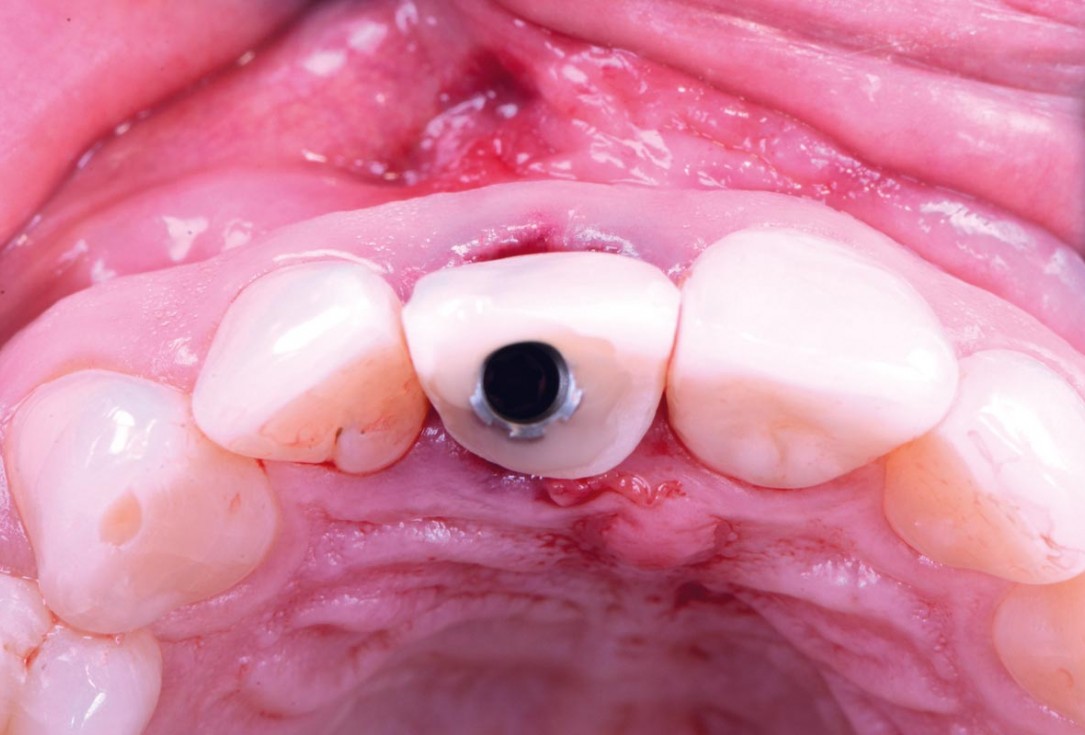

cerabone® and mucoderm® for immediate implantation in the aesthetic area - Dr. D. Robles

Initial clinical situation - Central incisors with dental destruction and periapical pathology